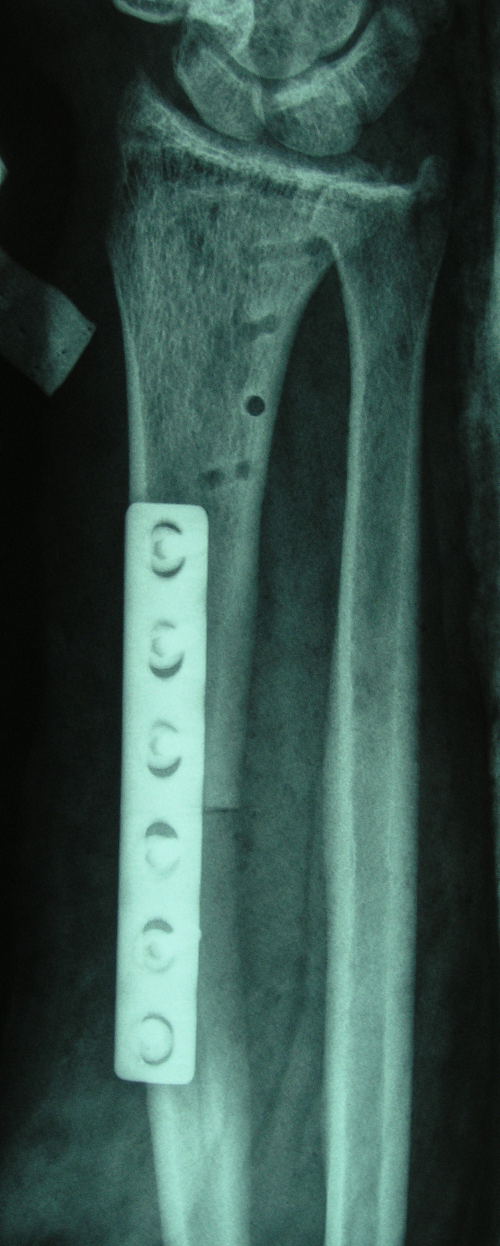

4.病例4:女 35岁, 右桡骨远端骨巨细胞瘤(Campanacci Ⅲ级),行瘤段广泛切除异体半关节移植术

图 15 术前X线片

a:正位

b:侧位

图 16 术后X线片 a:正位

b:侧位